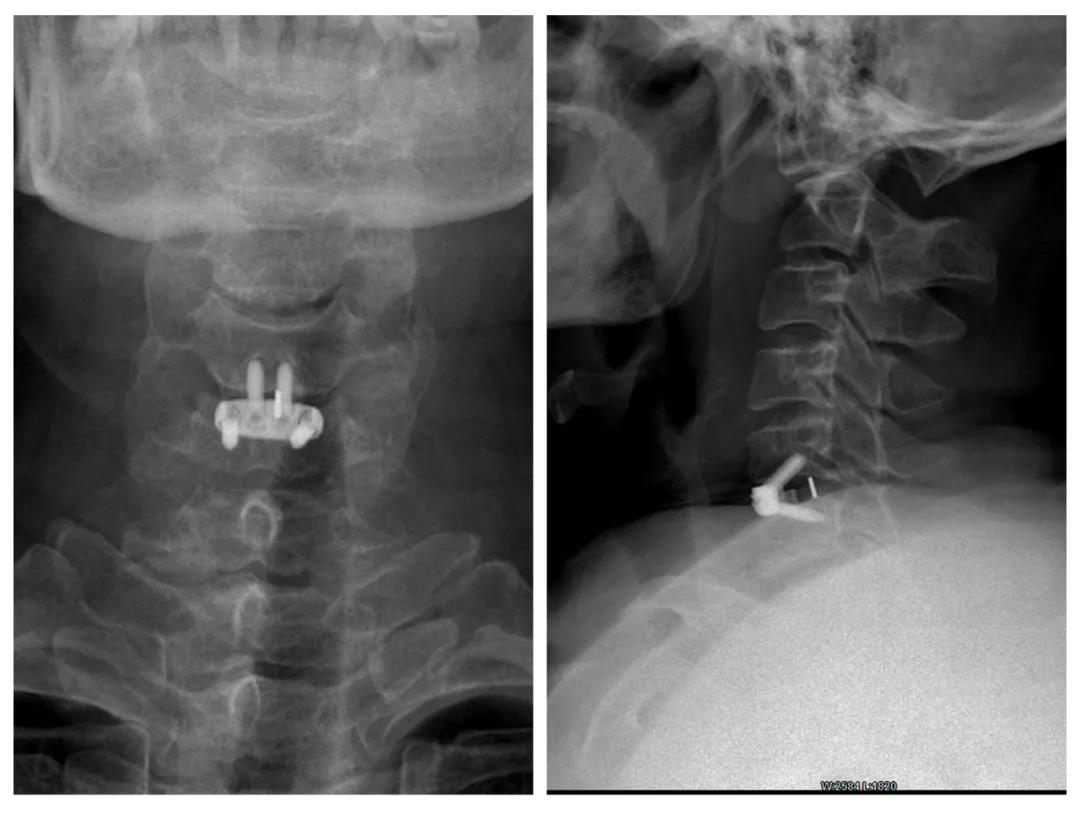

近日,我院骨科二病区团队在主任王胜利的带领下顺利开展了“零切迹”颈椎前路减压椎间融合手术,为颈椎病患者的治疗带来了新的选择,患者术后恢复良好,标志着我院骨科的诊疗技术迈上一个新的台阶。

因为已经出现神经压迫症状,四肢麻木、无力,严重影响患者生活。根据患者病情资料,鉴于患者年龄、颈髓受压、外伤等情况,考虑患者具有手术治疗指征,王胜利团队决定为其手术以达治疗目的。为了能让患者在一定程度

挽救脊髓功能、改善患者的生活,经科室讨论,放弃传统颈椎手术方法,决定为其采用新型“零切迹”椎间融合手术方案。